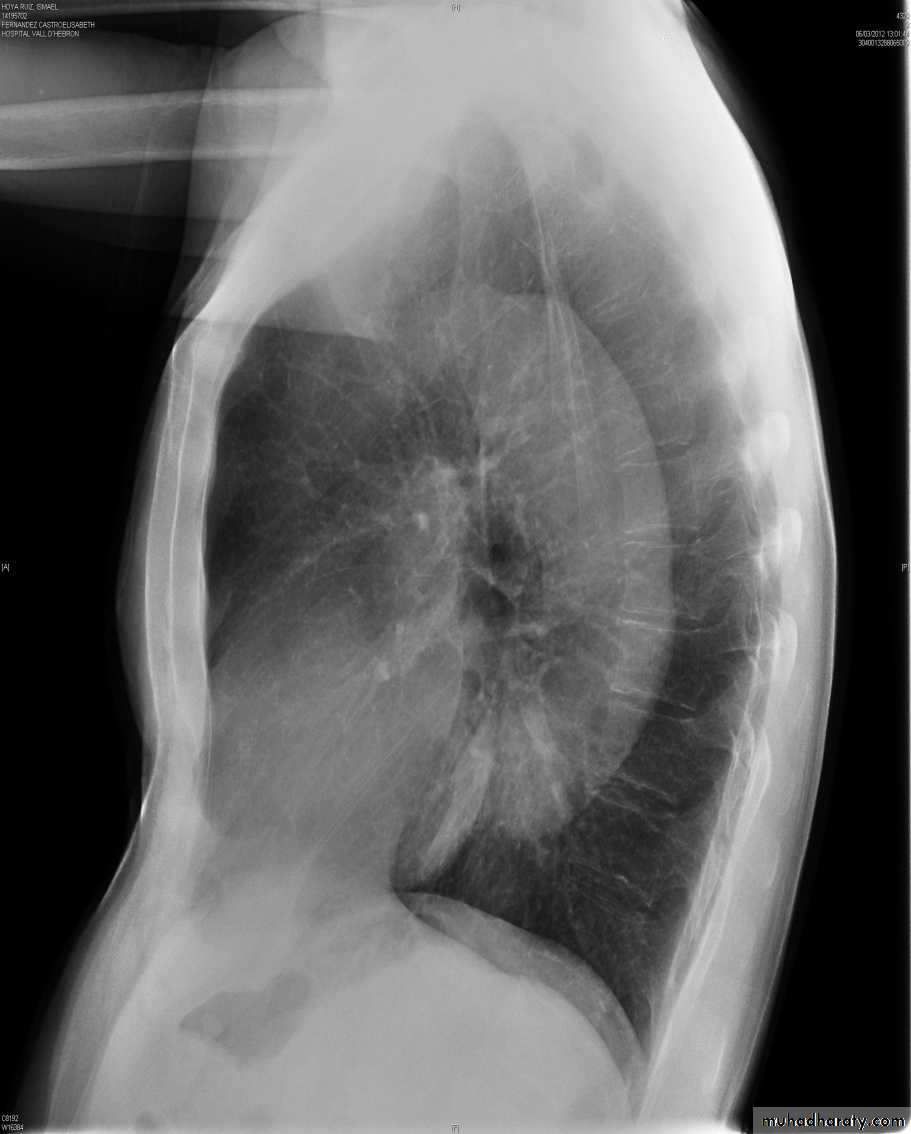

Frontal and lateral chest radiographs usually localize a mediastinal mass to a structure within the anterior, middle, or posterior mediastinal compartments. For instance, if the contours of a lesion are outlined by air and seen above the clavicles, then the lesion must be in the posterior mediastinum. Conversely, if the contours of a lesion are lost at the thoracic inlet level, it must be anterior

Posterior mediastinal lesions are seen on the lateral view projecting over the spine and are also paraspinous on the frontal chest x-ray. Most (90%) posterior mediastinal lesions are neurogenic.